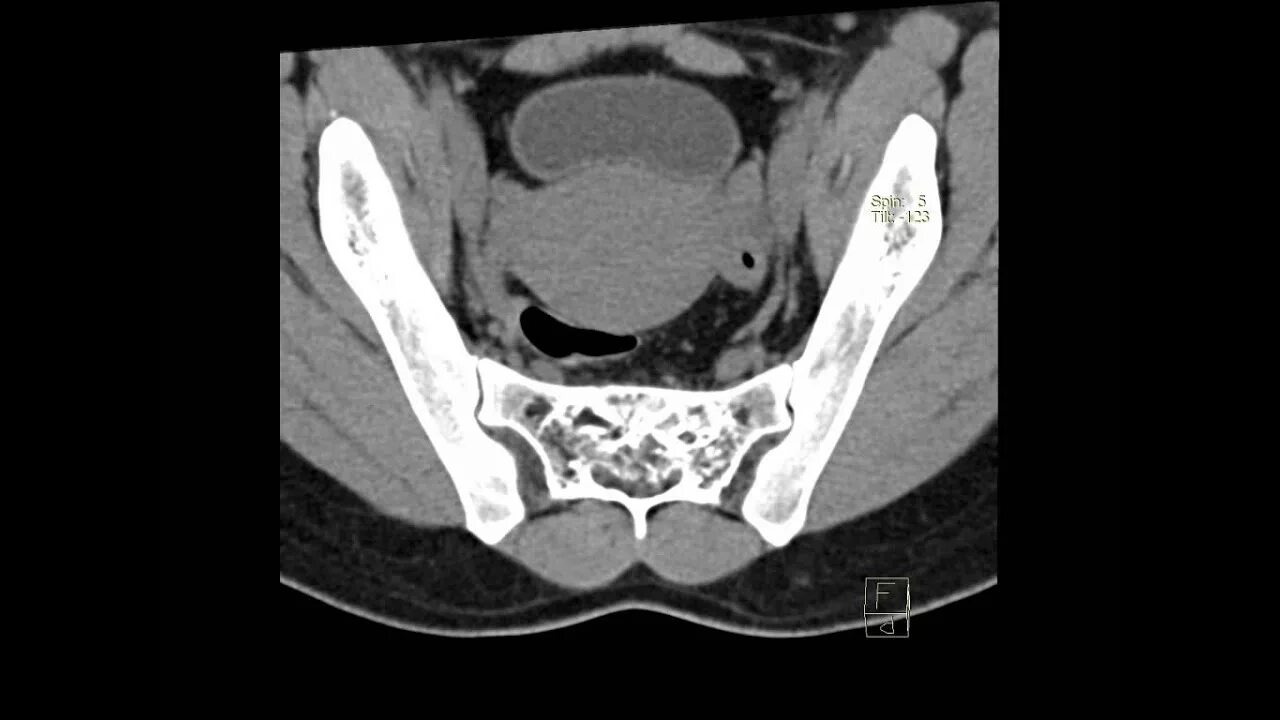

Метастазы в крестце